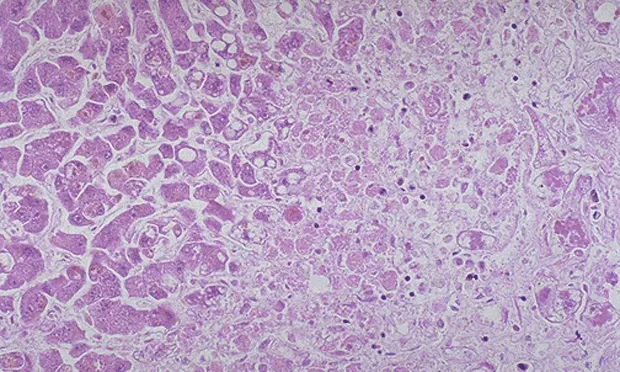

Acetaminophen administration in both dogs and cats leads to dose-dependent acute centrilobular hepatic necrosis (Figure 2). Dogs have similar susceptibility to acetaminophen toxicity as humans, with a toxic dose of 150 to 250 mg/kg. Acetaminophen is bioactivated to an oxidized metabolite by CYP2E1, a cytochrome P450 that is induced by phenobarbital; this reactive metabolite is detoxified by glutathione conjugation. Phenobarbital administration and glutathione depletion could therefore increase the risk for acetaminophen toxicity in dogs.

Figure 2. Liver necrosis caused by acetaminophen. Courtesy Sharon Gwaltney-Brant, ASPCA Animal Poison Control Center